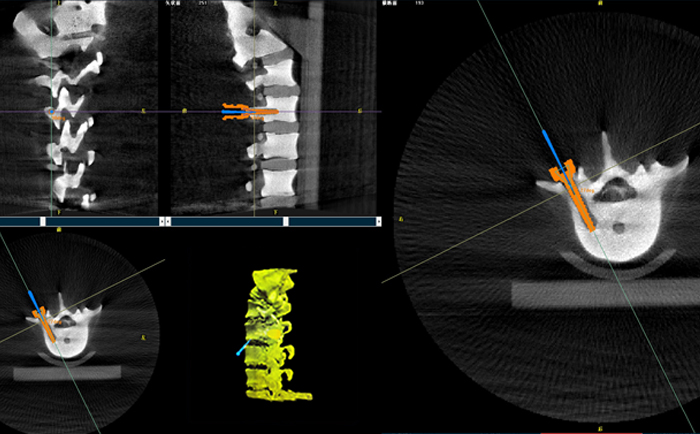

以椎弓根螺釘置入手術為例,傳統(tǒng)手術為了準確定位,需要將其多次進出反復選擇,增加了神經損傷與螺釘損壞的風險。但外科手術機器人可通過術前規(guī)劃把手術入路、方向、釘子深度都規(guī)劃好,基本做到一步到位,讓手術更加安全。

手術開始前,外科手術機器人與3D C形臂對患者的患處進行了一次掃描,做到“知己知彼”;接著電腦系統(tǒng)為每一顆螺釘設計出前進的路徑;隨后,“穩(wěn)如泰山”的機器人之手——機械臂,開始為每條路徑掃除障礙,猶如鋪設火車軌道;最后沿標準路徑置入螺釘,猶如火車行駛在車軌之上,最終準確置入螺釘。

普愛醫(yī)療的外科手術機器人經國家藥監(jiān)局批準,作為第三類醫(yī)療器械開始上市并應用于臨床,主要用于椎弓根螺釘內固定術、經皮穿刺椎體成形術等術式(包括頸椎、腰椎、胸椎等)等脊柱外科手術。輔助準確定位植入物或手術器械,精度達到亞毫米級,尤其對微創(chuàng)手術、高風險手術具有明顯優(yōu)勢,可有效降低手術風險、減少手術并發(fā)癥。